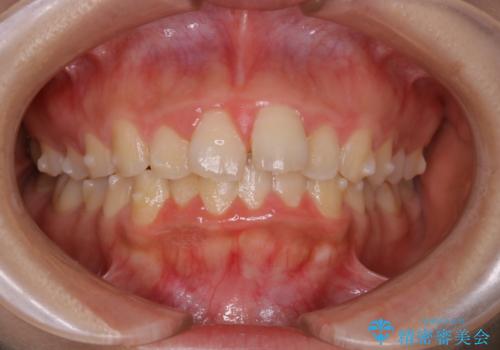

でこぼこの歯 / 上下の歯の真ん中を揃える

- 20代女性

- 歯のがたつきを主訴に来院。

初診時、下顎大臼歯は他院にて治療中の状態であった。

他院にて仮歯を入れ終わった後、当院で矯正治療へ。

上下の歯のサイズバランスを取るため、および上下の歯の正中を揃えるために、上下前歯部に歯のサイズダウンを行うことにした。

奥歯の咬み合わせの状態の良い、軽度叢生であったため、治療も短期間で終わらせることができました。